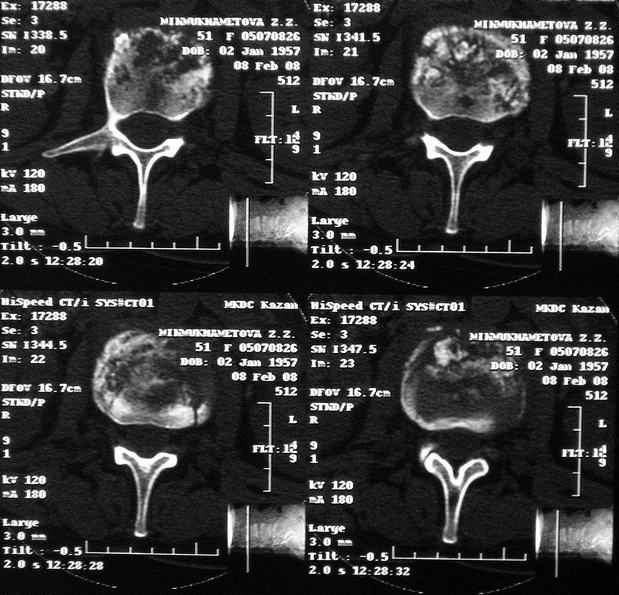

По данным представленных КТ и МРТ у больной имеется достаточно выраженная степень деструкции тел позвонков (около 30% общей костной массы тела позвонка), что определяет высокий риск возникновения патогических переломов и появления локальной кифотической деформации на этом уровне.

Судя по снимкам похоже идет речь о спинальном остеомиелите для диф диагноза стоит провести черезкожную пункционную биопсию(с помощью КТ)

Уважаемый доктор! судя по последнему МРТ процесс затрагивает соседние позвонки с переходом процесса через диск. Для туберкулёза как раз и характерна картинка "целующихся" позвонков. При бактериальном процессе диск страдает лишь вторично. Туберкулиновые пробы могут быть в пределах нормы, лёгкие - чистые. Вообще туберкулёз последнее время стал очень коварен и атипичен. Такие случаи отмечались у детей старшего возраста.